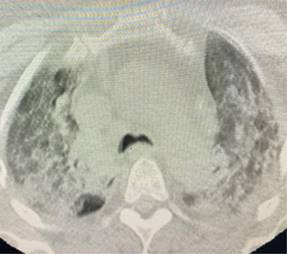

Presentamos una serie de casos de cuatro pacientes con SARS-CoV-2 con un compromiso importante de la oxigenación a pesar del uso de sistemas de alto flujo. En la Tabla 1 se describen grupos etarios, sexo, morbilidades, condiciones clínicas y escalas de severidad pronóstica de ingreso. Evolucionan tórpidamente frente al uso de cánula de alto flujo con índices de Rox por debajo de dos puntos en las primeras 12 horas.4 Se inicia ventilación mecánica no invasiva con progresión a falla respiratoria por aumento de la carga inspiratoria, por lo que requirieron protección de vía aérea. Se documenta un serio deterioro de la mecánica ventilatoria con sobredistención, aumento del trabajo respiratorio y caída de las distensibilidades; variables de monitoreo de la ventilación mecánica tomada en zona cero de flujo justo antes de cada inspiración. Adicionalmente evoluciona con importante deterioro de la ventilación minuto alveolar y de la oxigenación frente a la ventilación mecánica instaurada y a la posición prono, con poca tolerancia a la presión positiva direccionada por bucle presión volumen, meseta, fracción inspirada de oxígeno y curva presión tiempo.5-7 Con base en imágenes escanográficas que documentan infiltrados esmerilados, se describen cuatro campos pulmonares y zonas de condensación en las Figuras 1-4, además de compliance menor de 40 cm y requerimientos de PEEP entre 17 y 20 cm de agua, con el antecedente de volúmenes corregidos espiratorios durante la ventilación mecánica no invasiva entre 15 y 20 puntos se precisa SARS-CoV-2.8 Con base en la evolución descrita se decide instaurar protección pulmonar con 3 mL por kilogramo de peso más insuflación de gas traqueal con 5 L por min con el ánimo de ahorrar presión positiva de fin de espiración (PEEP por sus siglas en inglés positive end expiratory pressure), volumen tidal y velocidades de flujo. En la Tabla 2 se registra evolución gasimétrica antes y después de la estrategia. Se descartan coexistencias infecciosas de acuerdo al reporte de la microbiología. En los cuatro pacientes se documentaron defectos segmentarios de distribución vascular compatibles con enfermedad pulmonar tromboembólica. Evolucionan satisfactoriamente permitiendo desmontar estrategia de rescate con base en mecánica ventilatoria e índice de oxigenación,9 pudiendo implementar asa cerrada en asistencia proporcional con 40% de asistencia por flujo y volumen, PEEP de 10 cm y fracción inspirada de oxígeno de 50%. Se realizan monitoreos en asa cerrada que se muestran en la Tabla 3, documentándose trabajo respiratorio limítrofe, serio deterioro de las propiedades pulmonares mecánicas dinámicas y estáticas sin poder liberar de manera convencional, por lo que se programa para traqueostomía y traslado a cuidado crónico.

Figura 3: Infiltrados cuatro campos pulmonares y colecciones laminares bilaterales. Condensaciones posterobasales.